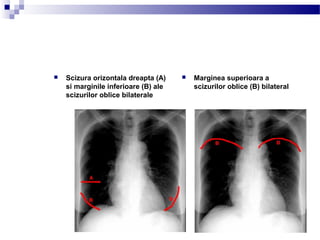

 Marginea superioara a

scizurilor oblice (B) bilateral

 Scizura orizontala dreapta (A)

si marginile inferioare (B) ale

scizurilor oblice bilaterale

 ambii plamani sunt suprapusi,

luati separat, plamanul stang

are o singura fisura oblica

 plamanul drept are ambele

fisuri, oblica si orizontala